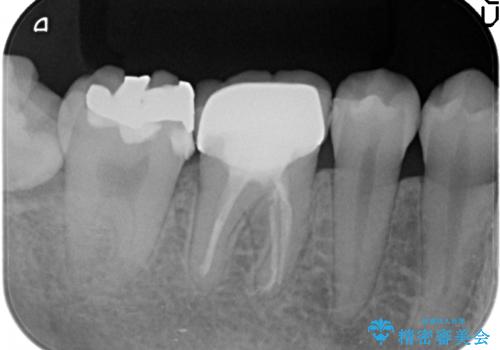

- 右下7の銀歯を白くしたいといらっしゃった方の症例です。

銀歯及び虫歯を除去後、セラミックインレーで修復を行いました。

当院のセラミックインレーはemaxという強度と審美性に優れた材料を使用しています。

またプレス方式でインレーを製作しているため、削り出しで製作するCADCAMより優れた適合性も持ち合わせており、虫歯が再発しにくい修復物です。